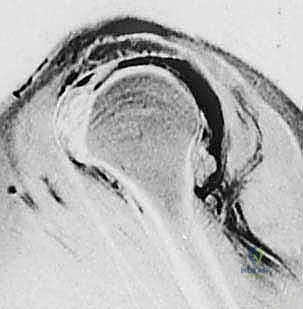

- الرنين المغناطيسي (MRI): هو المعيار الذهبي. يوضح الرنين المغناطيسي حجم التمزق، موقعه، مدى تراجع (انسحاب) الوتر، وما إذا كان هناك ضمور دهني في العضلة.